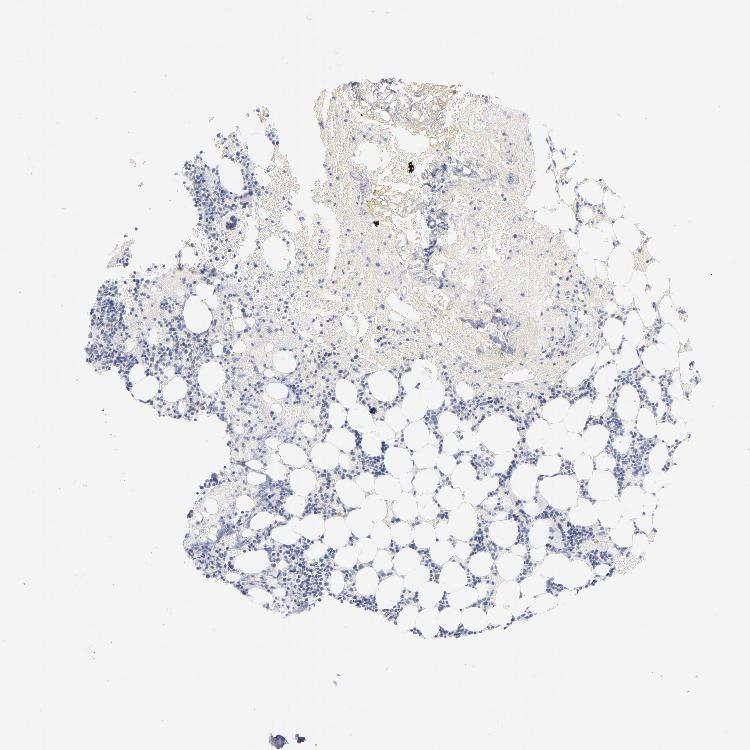

TISSUE PRIMARY DATA BONE MARROW Show tissue menu

BONE MARROW - Antibody stainingi

Antibody staining in the annotated cell types in the current human tissue is reported as not detected, low, medium, or high, based on conventional immunohistochemistry profiling in selected tissues. This score is based on the combination of the staining intensity and fraction of stained cells.

Each image is clickable and will lead to virtual microscopy that enables deeper exploration of all samples and also displays staining intensity scores, fraction scores and subcellular localization as well as patient and tissue information for each sample.

Antibody HPA003402

Hematopoietic cells Not detected